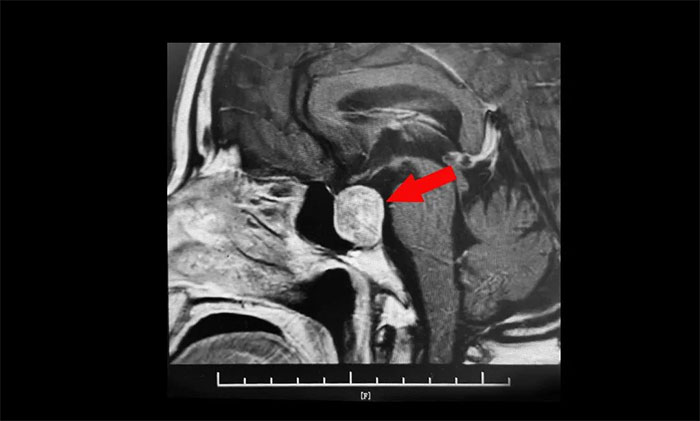

鞍區(qū)MRI平掃+增強(qiáng)顯示:蝶鞍顯著擴(kuò)大,鞍區(qū)見(jiàn)腫塊信號(hào),大小約29*19*24mm;垂體柄明顯縮短左偏;病變向鞍上生長(zhǎng),占據(jù)鞍上池,推移視交叉;向鞍旁生長(zhǎng),侵及右側(cè)海綿竇,右側(cè)海綿竇內(nèi)頸內(nèi)動(dòng)脈被推壓、包繞,右側(cè)頸內(nèi)動(dòng)脈海綿竇段較對(duì)側(cè)稍細(xì)。

▲ 腫瘤侵襲生長(zhǎng),包繞頸內(nèi)動(dòng)脈,knosp分級(jí)Ⅲ級(jí)

針對(duì)該患者,治療方式就是手術(shù)切除腫瘤,減除腫瘤壓迫。目前手術(shù)方式,主要有開(kāi)顱手術(shù)切除腫瘤和經(jīng)單鼻孔-蝶竇入路切除腫瘤。而該患者腫瘤如鴿子蛋大小,屬于垂體大腺瘤,并且侵襲生長(zhǎng),侵及右側(cè)海綿竇,右側(cè)海綿竇內(nèi)頸內(nèi)動(dòng)脈被推壓、包繞,knosp分級(jí)Ⅲ級(jí),向上已突破鞍隔壓迫視神經(jīng)、視交叉、下丘腦;向下侵蝕充滿蝶竇。